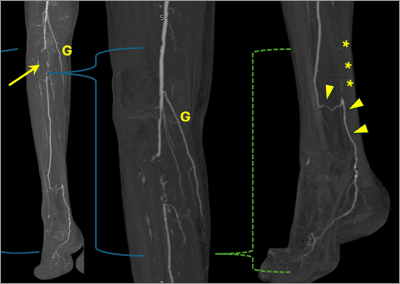

81-year-old female status post previous Edwards Sapien transcatheter aortic valve replacement (TAVR), now presenting with recurrent symptoms of valvular aortic stenosis.

Figure 1.

A. Multiplanar reconstruction orthogonal to TAVR prosthesis, systolic phase (30% R-R interval). There is hypoattenuating leaflet thickening (HALT), most pronounced involving the right and non-coronary leaflets (arrowheads). The left leaflet (L) is less affected.

B. Blood pool inversion (BPI) volume rendering (VR) in same orientation as (A) shows restricted leaflet motion (RELM).

Video 1: BPI VR cine imaging shows HALT that results in RELM that is severe (>70% restriction) involving the right and noncoronary leaflets and mild (<50%) involving the left leaflet. Combination of HALT and RELM is considered hypoattenuation affecting motion (HAM).